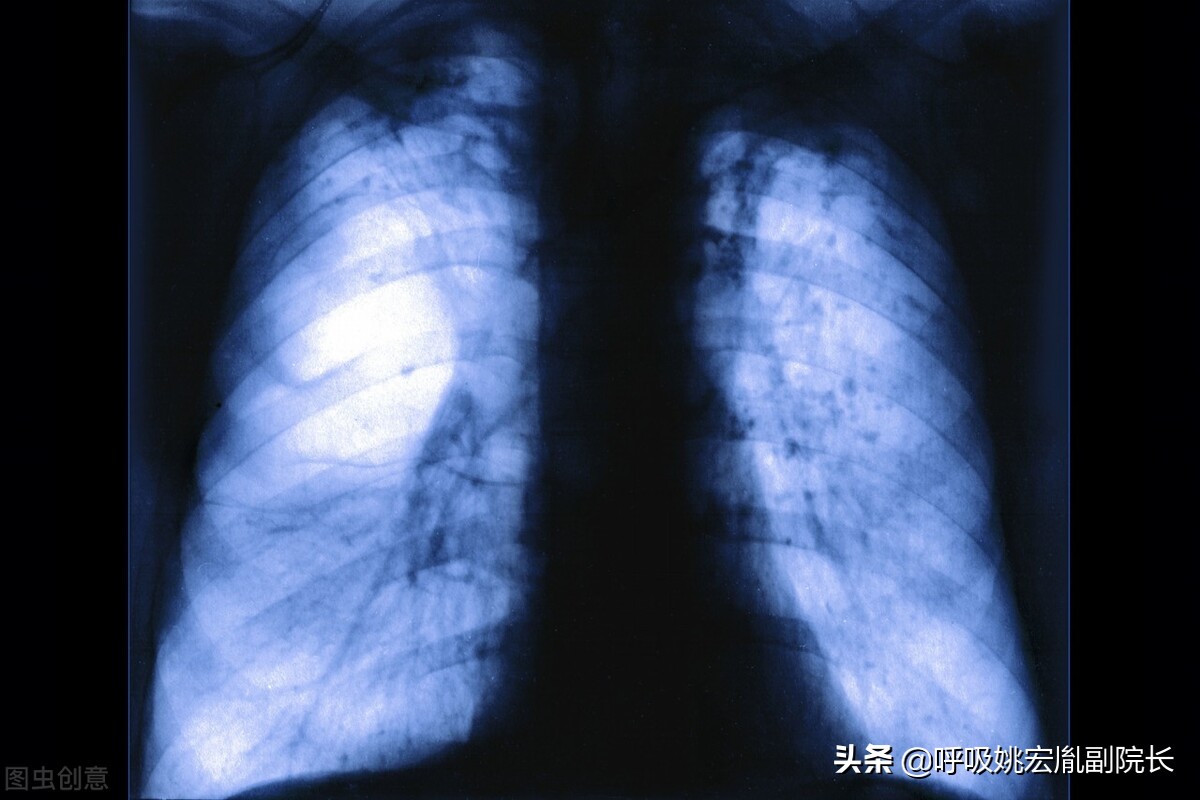

肺气肿:肺气肿是指终末细支气管远端的气道弹性减退,过度膨胀、充气和肺容积增大或同时伴有气道壁破坏的病理状态。按其发病原因肺气肿有如下几种类型:老年性肺气肿、代偿性肺气肿、间质性肺气肿、灶性肺气肿、旁间隔性肺气肿、阻塞性肺气肿。

肺结节:肺结节是指在肺实质内而不属于正常肺组织的结节状阴影,直径小于3厘米,其中直径小于1厘米的称之为小结节,直径小于3毫米的称之为微结节,而大于3厘米的我们称之为肿块。肺结节可以表现为单独一个,也可以是多个。80%-90%以上的肺结节都是良性的,当然也有一部分结节是恶性的,而少数肺良性结节在随访的过程中可能会出现恶变。